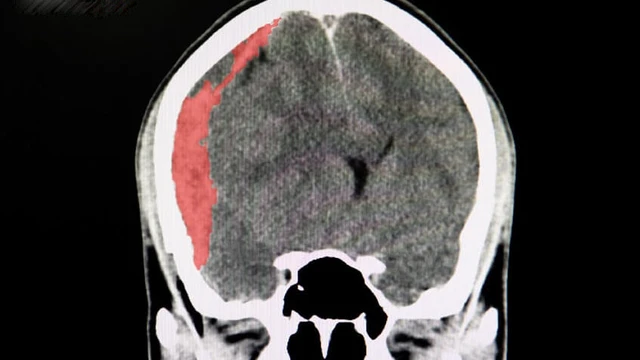

Xuất huyết nội sọ là tình trạng chảy máu trong hộp sọ do vỡ mạch máu não. Đây là một cấp cứu y khoa nghiêm trọng có thể gây tổn thương não vĩnh viễn hoặc đe dọa tính mạng nếu không được xử lý kịp thời.

Chấn thương não, chẳng hạn như tụ máu não, thường đe dọa tính mạng và cần được chăm sóc y tế ngay lập tức. Khi gặp phải tình trạng này, hầu hết bệnh nhân và gia đình họ thường băn khoăn không biết một người bị tụ máu não sống được bao lâu và tiên lượng ra sao. Bài viết sau đây sẽ cung cấp thông tin chi tiết để giải đáp những thắc mắc này.